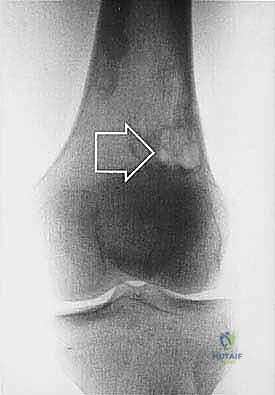

* الساركوما العظمية (Osteosarcoma): الأكثر شيوعاً، تظهر عادة حول الركبة (أسفل الفخذ أو أعلى القصبة).

| حدود الورم في الأشعة | واضحة، محددة بدقة (Sclerotic margin) | غير واضحة، متآكلة (Moth-eaten appearance) |

| اختراق قشرة العظم | نادر جداً | شائع جداً، يمتد للأنسجة الرخوة المحيطة |

تحديد مراحل الورم (Staging): نظام Enneking

تحديد مرحلة الورم هو الخطوة الأهم قبل أي تدخل جراحي. يعتمد الدكتور هطيف على نظام (Enneking) لتحديد مراحل أورام العظام، والذي يعتمد على ثلاثة عوامل: